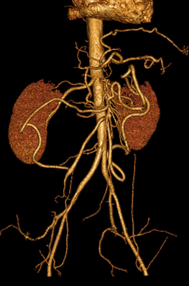

Cancers colo-rectaux

DANSE E. - UCL

Digestif MASTER 1